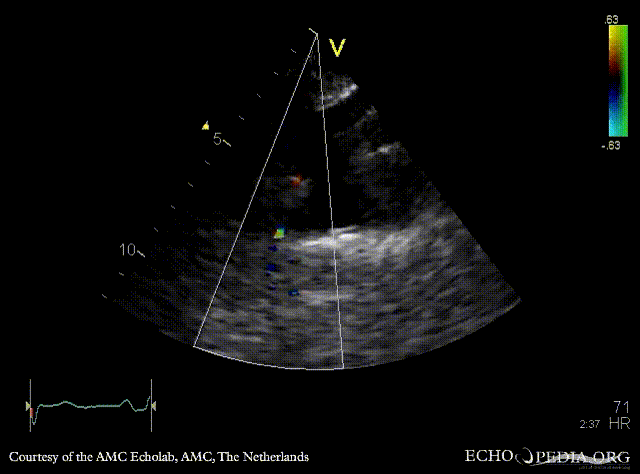

Coarctatio aortae

Courtesy of: AMC Echolab, AMC, The Netherlands

E00361.gif E00362.gif

Suprasternal view Suprasternal view: Collor Doppler, high velocity flow in descending aorta